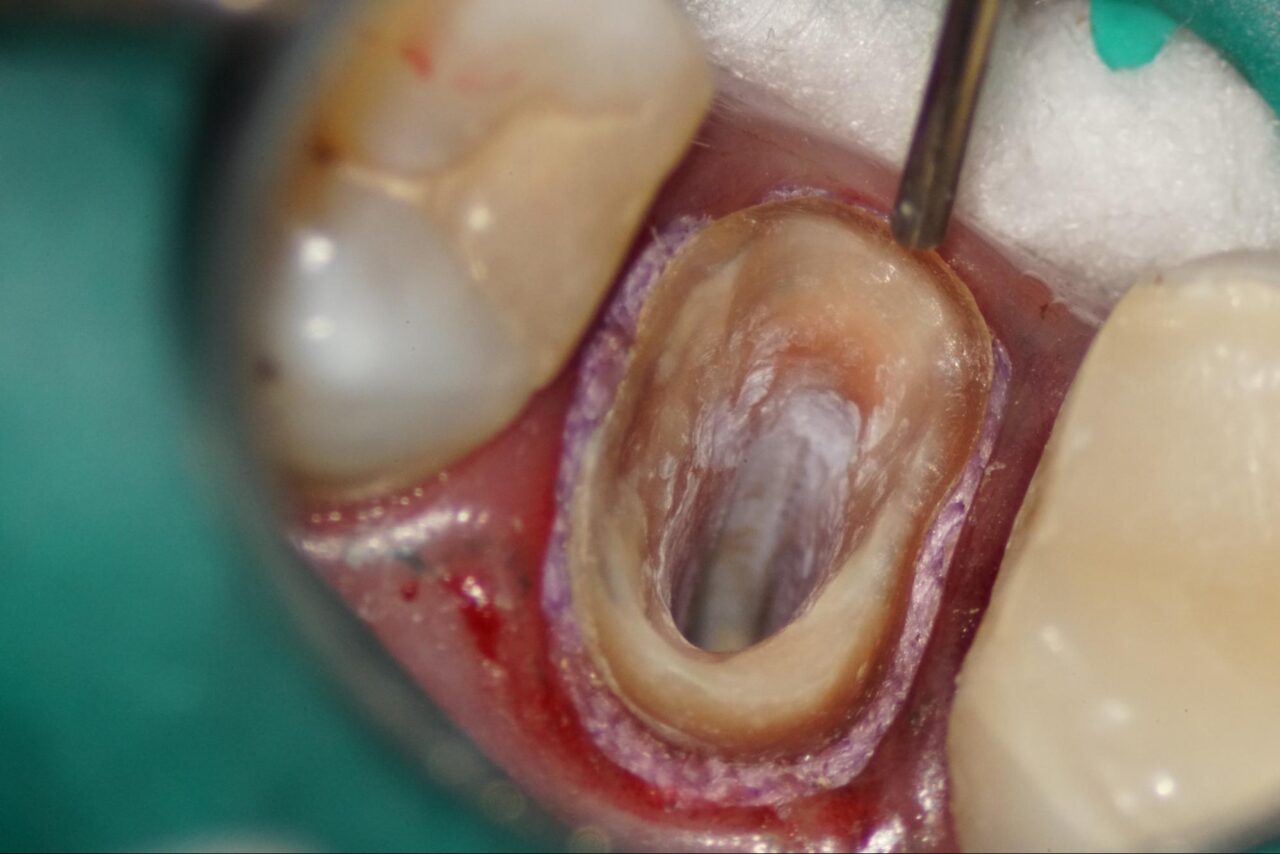

症例2:膿の道、サイナストラクトが存在している歯

膿の道、サイナストラクトが存在している歯では、多くの場合再発、再治療の事が多くあります。

通法通りに先ずは麻酔をします膿の道の部分をさせて、麻酔の針を刺します。これは麻酔薬が膿の道から漏れない様の周辺から麻酔を進めます。

その後、ラバーダムアイソレーションを行いますが、患歯との間に何かエラーがあるためラバーシートが入って行きません。